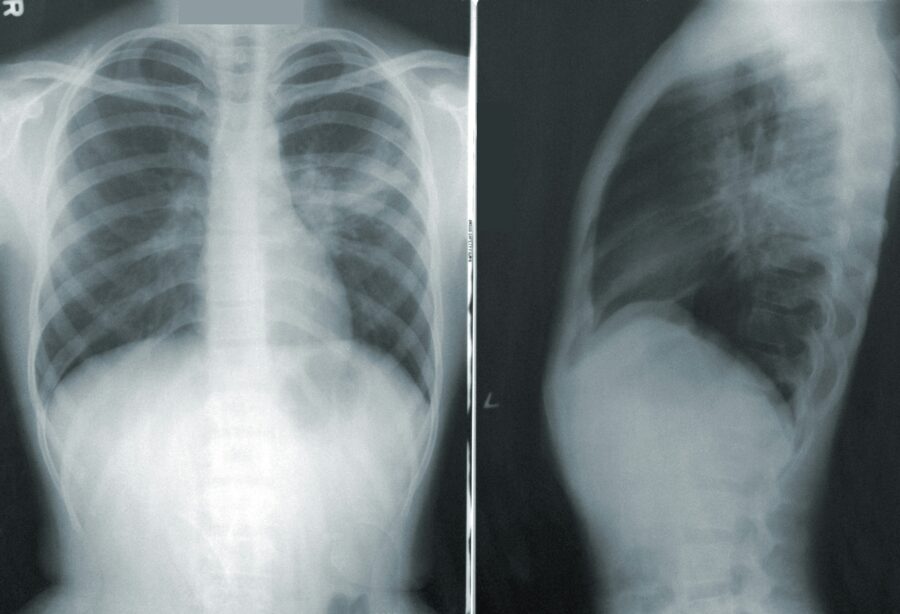

LIJEČNICI SAVJETUJU CIJEPLJENJE / Sve više oboljelih od atipične upale pluća: Obratite pozornost na ove simptome

Raste broj slučajeva upale pluća tijekom ljeta. Sve više oboljelih bilježe šibenska Opća bolnica i zagrebačka Klinika za infektivne bolesti dr. Fran Mihaljević. Pogotovo zabrinjava jedna vrsta koju je zbog atipičnih simptoma teže dijagnosticirati.

Neobično za ljeto, povećava se broj pacijenata s upalom pluća.

Pogotovo onih s atipičnom upalom koju uzrokuje bakterija mikoplazma.

Prvi simptom atipične upale pluća obično je povišena tjelesna temperatura, ne previsoka. Zatim se javljaju suh kašalj, bol u prsima, kratkoća daha, umor, glavobolja. Simptomi su često neobični za upalu pluća. Može doći i do upale mozga, kožnih osipa ili nekog poremećaja svijesti. Prenosi se kapljičnim putem.

“To su uzročnici koji imaju neke simptome koji mogu biti nepovezani s pneumonijom, zato što ti uzročnici uzrokuju simptome sami za sebe. Često pacijenti znaju reći da povraćaju od kašlja što nije tipično za običnu upalu pluća. Tako da svašta se tu zna naći”, objsnio je liječnik Juraj Jug.

Atipična upala pluća krajem prošle godine počela se češće pojavljivati u Aziji i nekim europskim zemljama. U Klinici Fran Mihaljević porast bilježe već nekoliko mjeseci.

“Na sreću prolazi ambulatno, ili kroz naše dnevne bolnice, ali ima onih s težim kliničkim formama bolesti osobito kad govorimo o dječjoj populaciji koji su liječeni bolnički praktički s intenzivnim metodama liječenja u pojedinim situacijama”, rekao je Barišić.